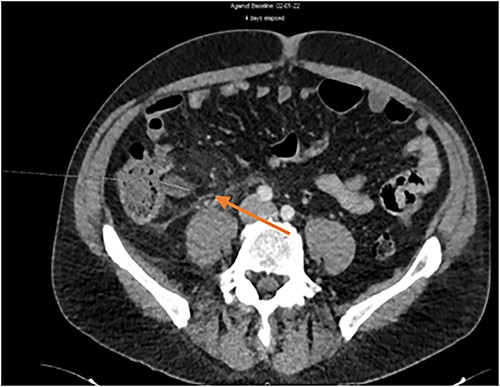

In total, 24 h later, the laboratory confirmed positive admission blood cultures (8/8 samples) for multi-sensitive Escherichia coli and Enterococcus faecalis. On postoperative day 3, despite appendicectomy and appropriate antibiotics, the patient presented with recurrent pyrexia (>38°C) and pain in the RIF. Therefore, a second abdominal scanner was performed and identified a thrombosis of the ileocolic vein associated with significant peripheral fat inflammation (Fig. 3).

The blood cultures were repeated. Because of endovascular infection, amoxicillin-clavulanic acid was discontinued and targeted antibiotic therapy was switched to ceftriaxone with amoxicillin and metronidazole. Finally, as the new blood cultures were positive for both multi-sensitive E. coli and extended-spectrum-beta-lactamase E. coli, a second switch with piperacillin and tazobactam was initiated. The treatment was prolonged for a total of 4 weeks from the first negative blood cultures (postoperative day 4). Anticoagulation was not administered in this case because of the small size of the phlebitis, the rapidly favourable clinical and biological evolution and the absence of liver complications. Subsequently, the evolution remained favourable.